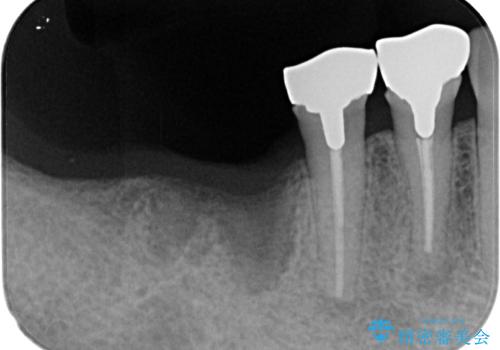

- 「歯を抜いたので、インプラントを入れてほしい」という主訴で来院された患者様です。

他院で歯根破折により抜歯をしたとのことでした。

CTにより残存骨量を確認しインプラント埋入を行っていくこととしました。

今後手前の根管治療を行っている歯が歯根破折を起こして抜歯になる可能性を想定して手前の歯に平行にインプラント埋入を行っています。